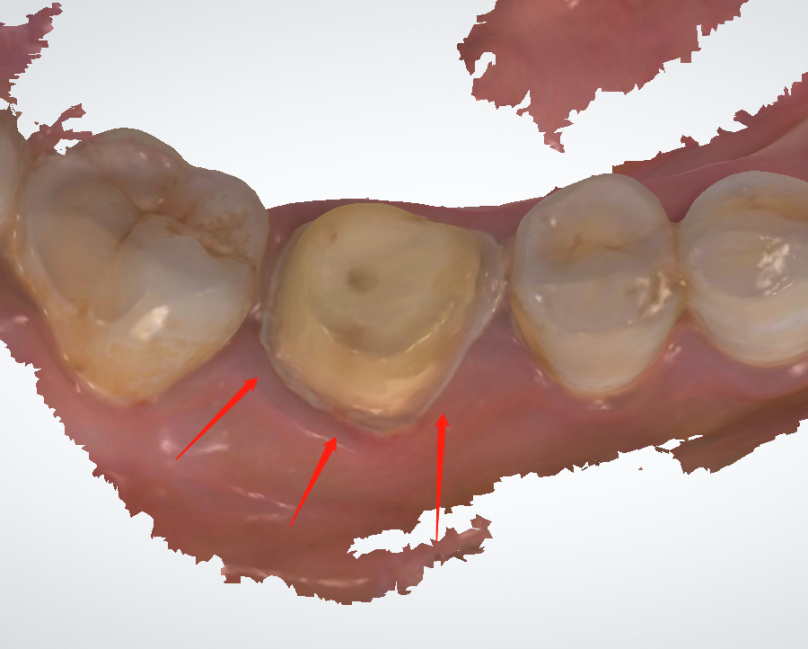

We can see the margin is much better in pic1 than what we see from pic2. And there is a little spot of the margin covered by the gum tissue. The margin is blur while the scanning is switched to pain color view.

In fact, the gingival retraction is not done properly. At the other hand, as an experienced technician, who should communicate with doctor before processing the case.

Solution to the problem: It needs a new oral scanning after make the gingival retraction in clinic. At the same time, to avoid the same problem to happen again, our customer service and technicians will check the oral scanning before processing.